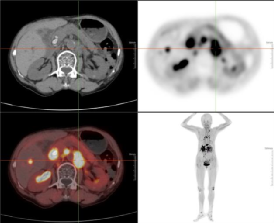

例二:79岁老年女性,胆囊结石7年,现反复腹痛待查,临床高度怀疑胰腺癌。传统影像学检查未能明确病灶边界与转移范围,通过18F-FAPI PET/CT显像,确诊为肝左外叶肝内胆管细胞癌(ICC),左侧锁骨旁、纵隔内(4R、4L、5、6、7)及双侧肺门、腹腔内、肝胃间隙、腹膜后、腹主动脉左旁、盆腔内多发淋巴结转移灶,胰腺及腹主动脉受侵。

新型分子探针18F-FAPI清晰呈现了原发灶及转移灶的精准位置、大小及周围组织侵犯情况,同时发现了隐匿的转移灶,为临床制定个体化治疗方案提供了关键依据。为肿瘤患者病灶的精准识别带来福音,为临床及时调整治疗策略、改善预后创造了条件。